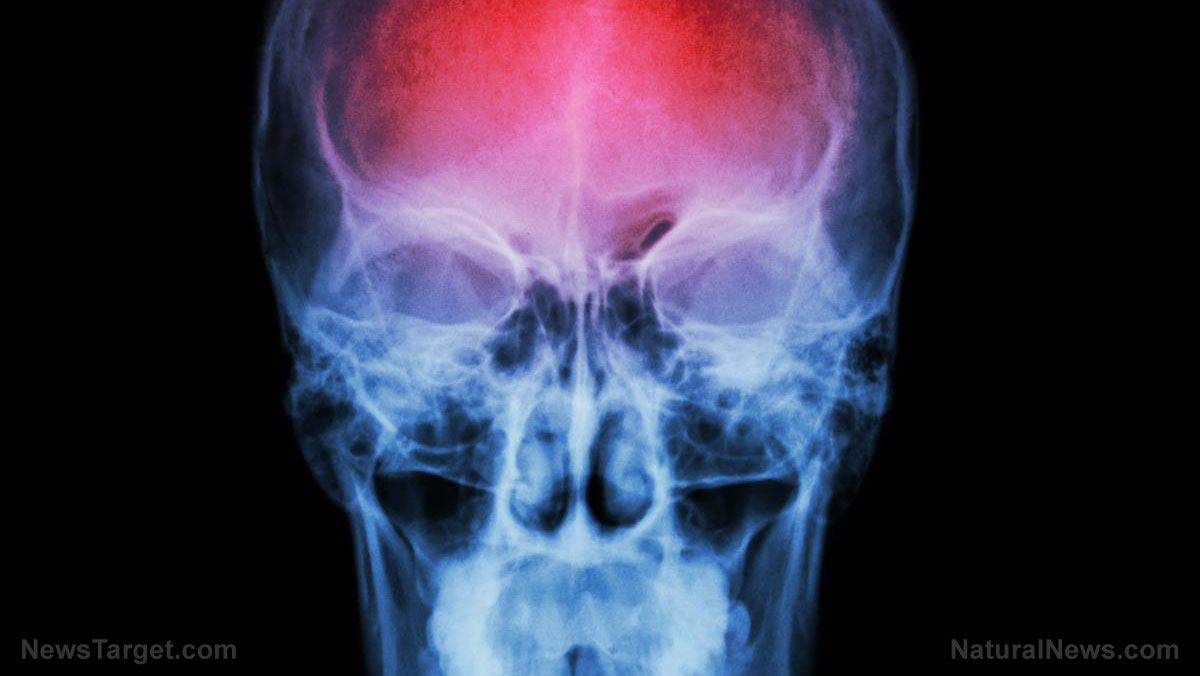

- A study warns that even mild exercise (e.g., brisk walking) can trigger strokes in people with carotid artery stenosis.

- Strenuous exercise increases blood pressure, dislodging plaques in severely blocked arteries and raising stroke risk.

- Simulations show intense exercise doubles shear stress on plaque, increasing rupture chances — debris can travel to the brain, causing stroke.

- Past studies link heavy exertion and emotional stress (anger and upset) to higher stroke odds, especially intracerebral hemorrhage.

In a world where personal health and well-being are paramount, a recent study has uncovered a hidden danger that could be affecting millions of Americans. The research suggests that for individuals with carotid artery stenosis, a condition affecting approximately five percent of the population, even simple exercises like a brisk walk or a Zumba class could trigger a stroke. This alarming finding raises critical questions about the safety of exercise for those at risk and the need for greater awareness and caution.